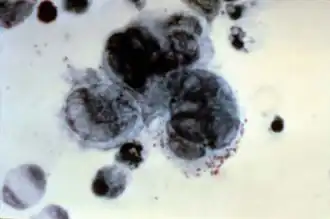

A positive Tzanck test, showing three multinucleated giant cells ("Tzanck cells") in center. | |

Acantholytic cell and multinucleated giant cell on a smear taken from a vesicular lesion of herpes simplex infection (May-Grünwald Giemsa x1000).

Acantholytic cell and multinucleated giant cell on a smear taken from a vesicular lesion of herpes simplex infection (May-Grünwald Giemsa x1000). -